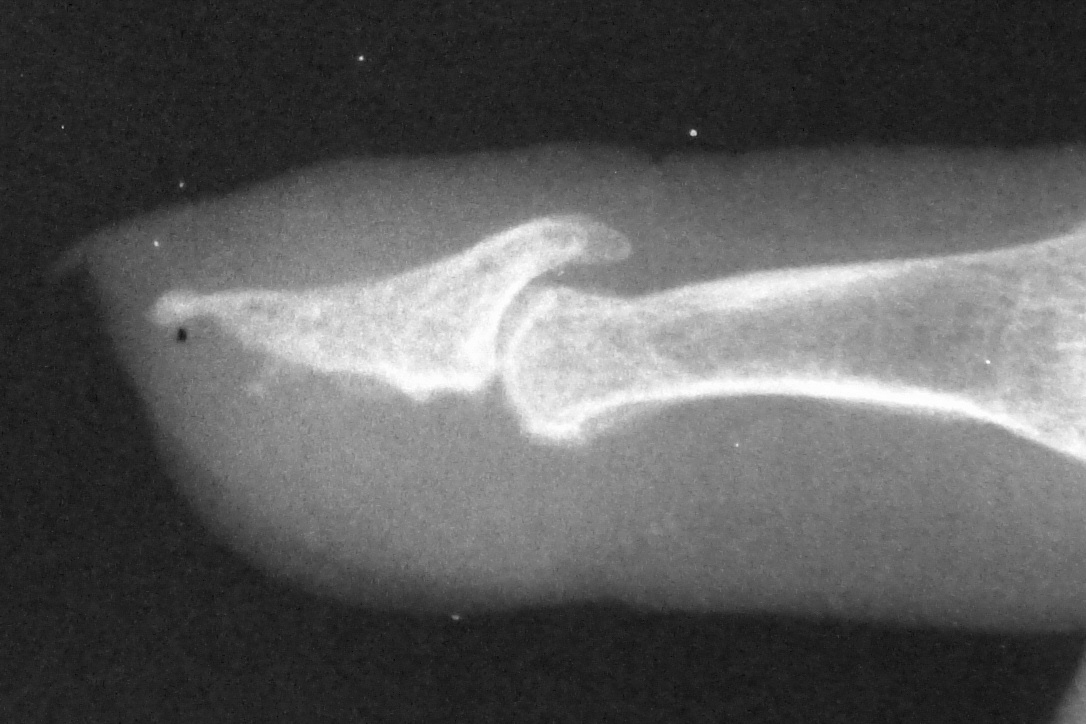

Xrays over this period: initial deformity, bone graft, and progressive bone graft loss over the course of years:

Image Image